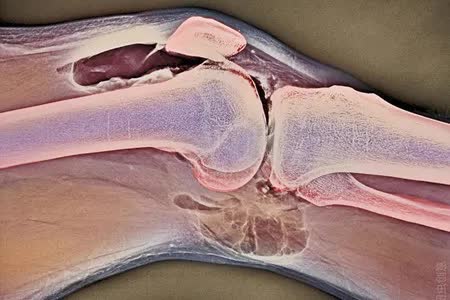

类风湿关节炎是一种以累及全身关节为主的疾病,主要表现为慢性、对称性、进行性多关节炎、关节滑膜炎症、淋巴细胞浸润、血管翳形成并增生、关节软骨与骨的侵蚀等,最终导致骨破坏。

骨破坏是造成类风湿患者关节畸形、功能丧失、关节破坏和全身性骨丢失等诸多临床问题的核心因素,也是使人丧失劳动能力和致残的“元凶”之一。

多种细胞参与骨破坏,其中破骨细胞是关节破坏的最主要细胞。而破骨细胞起源于骨髓的多能干细胞,类风湿炎症因子可直接促进破骨细胞分化。